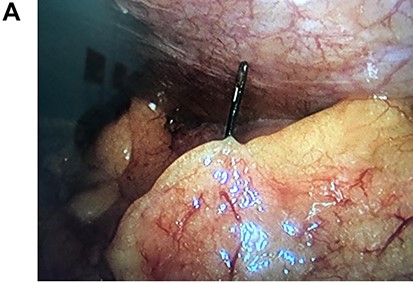

Leukocytosis with neutrophilia was detected, along with an elevated C-reactive protein. On the CT, a high-density object was seen in the descending colon; the object resembled a 4.5 cm needle that perforated the whole extent of the colonic wall. Surrounding this area there was inflammation with mesenteric edema. No lymph nodes or other masses were detected (Fig. 1A, 1B, 1C).

On laparoscopy, multiple adhesions between the omentum and descending colon were seen and released using an ultrasonic energy device (Harmonic, Ethicon US, LLC., Cincinnati, OH, USA). After mobilization of the left colon, the needle was seen stabbing the colonic wall 7 cm away from the splenic flexure. The needle was removed, and the perforation was sutured using a 2-0 absorbable suture without any complications. No other perforations were seen, and the procedure was completed without any complications (Fig. 2A, 2B).